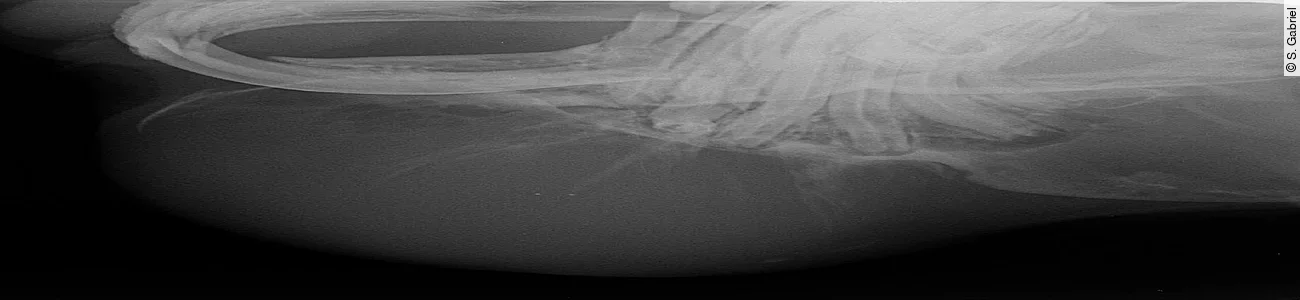

Ausgehend von einer Zahnwurzelentzündung (etwa durch unsachgemäßes „Abknipsen“ oder durch parodontal eingespießtes Fremdkörpermaterial, wie z. B. hölzerne Pflanzenfasern) kommt es zur eitrigen Alveolitis, die ihren Ausgang – der Schwerkraft folgend – nach ventral sucht, wenn der Zahn noch in der Alveole festsitzt. Osteolyse und Osteomyelitis durch pyogene Bakterien reizen den Körper zu einer fulminanten Entzündung mit Bildung einer dicken Demarkation, der sog. pyogenen Membran. Parallel zu lytischen Prozessen, die die Spongiosa des Unterkieferknochens auflösen ([Abb. 1]), kommt es zu stabilisierenden Knochenauftreibungen durch eine periostale Reaktion, oft mit blasenförmiger Auftreibung ([Abb. 1 a] und [1 b]) und in Form von radspeichenartigen Spiculae des Periostes ([Abb. 1 c]).

Abb. 1a-c

Handelt es sich um einen teilweise mit dem Periost verwachsenen oder bis in die Unterkieferspongiosa reichenden Abszess, ist die vorsichtige Resektion der Kapsel bis aufs Periost zu empfehlen. Mit einem scharfen Löffel kürettiert man danach die im Knochen liegenden Anteile der Abszesskapsel ([Abb. 3 a]). Falls die Kapsel an ihrer Basis durch periostale Auftreibungen schon knöchern durchgebaut ist, können die ossifizierten Anteile des Periosts mithilfe einer Luerschen Zange („Mini-Friedmann“) reseziert werden ([Abb. 3 b]). Dabei ist grundsätzlich darauf zu achten, die Stabilität des Unterkiefers nicht weiter zu reduzieren und nur vorragende Knochenspitzen für eine bessere Wundheilung abzusetzen. Auch für diese Entscheidung ist eine gute Röntgendarstellung unabdingbar ([Abb. 1]).